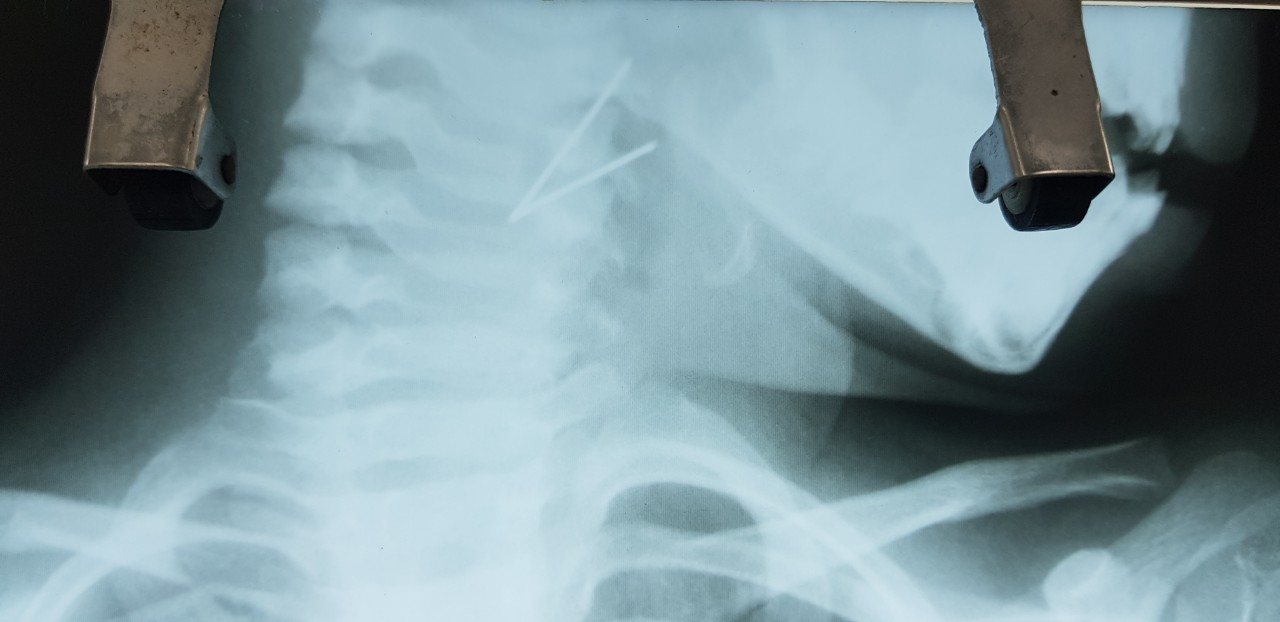

Bé gái được chuyển đến từ bệnh viện tuyến dưới trong tình trạng cổ nghiêng về bên phải không xoay sang trái được, đau, khó nuốt. Kết quả chụp Xquang cổ phát hiện, có một đoạn kim loại hình chữ V ở hạ họng bệnh nhi.

Đoạn kim loại trong cổ họng bé gái. Ngay sau đó, các bác sĩ đã nhanh chóng tiến hành nội soi lấy dị vật cấp cứu cho bé. Quá trình thực hiện, ekip lấy ra trong cổ họng bé gái dị vật là 1 đoạn kim loại dài 7cm hình chữ V gập góc, một đầu cài vào thành bên họng trái, đỉnh chữ V chặn ngay xoang lê bên trái.